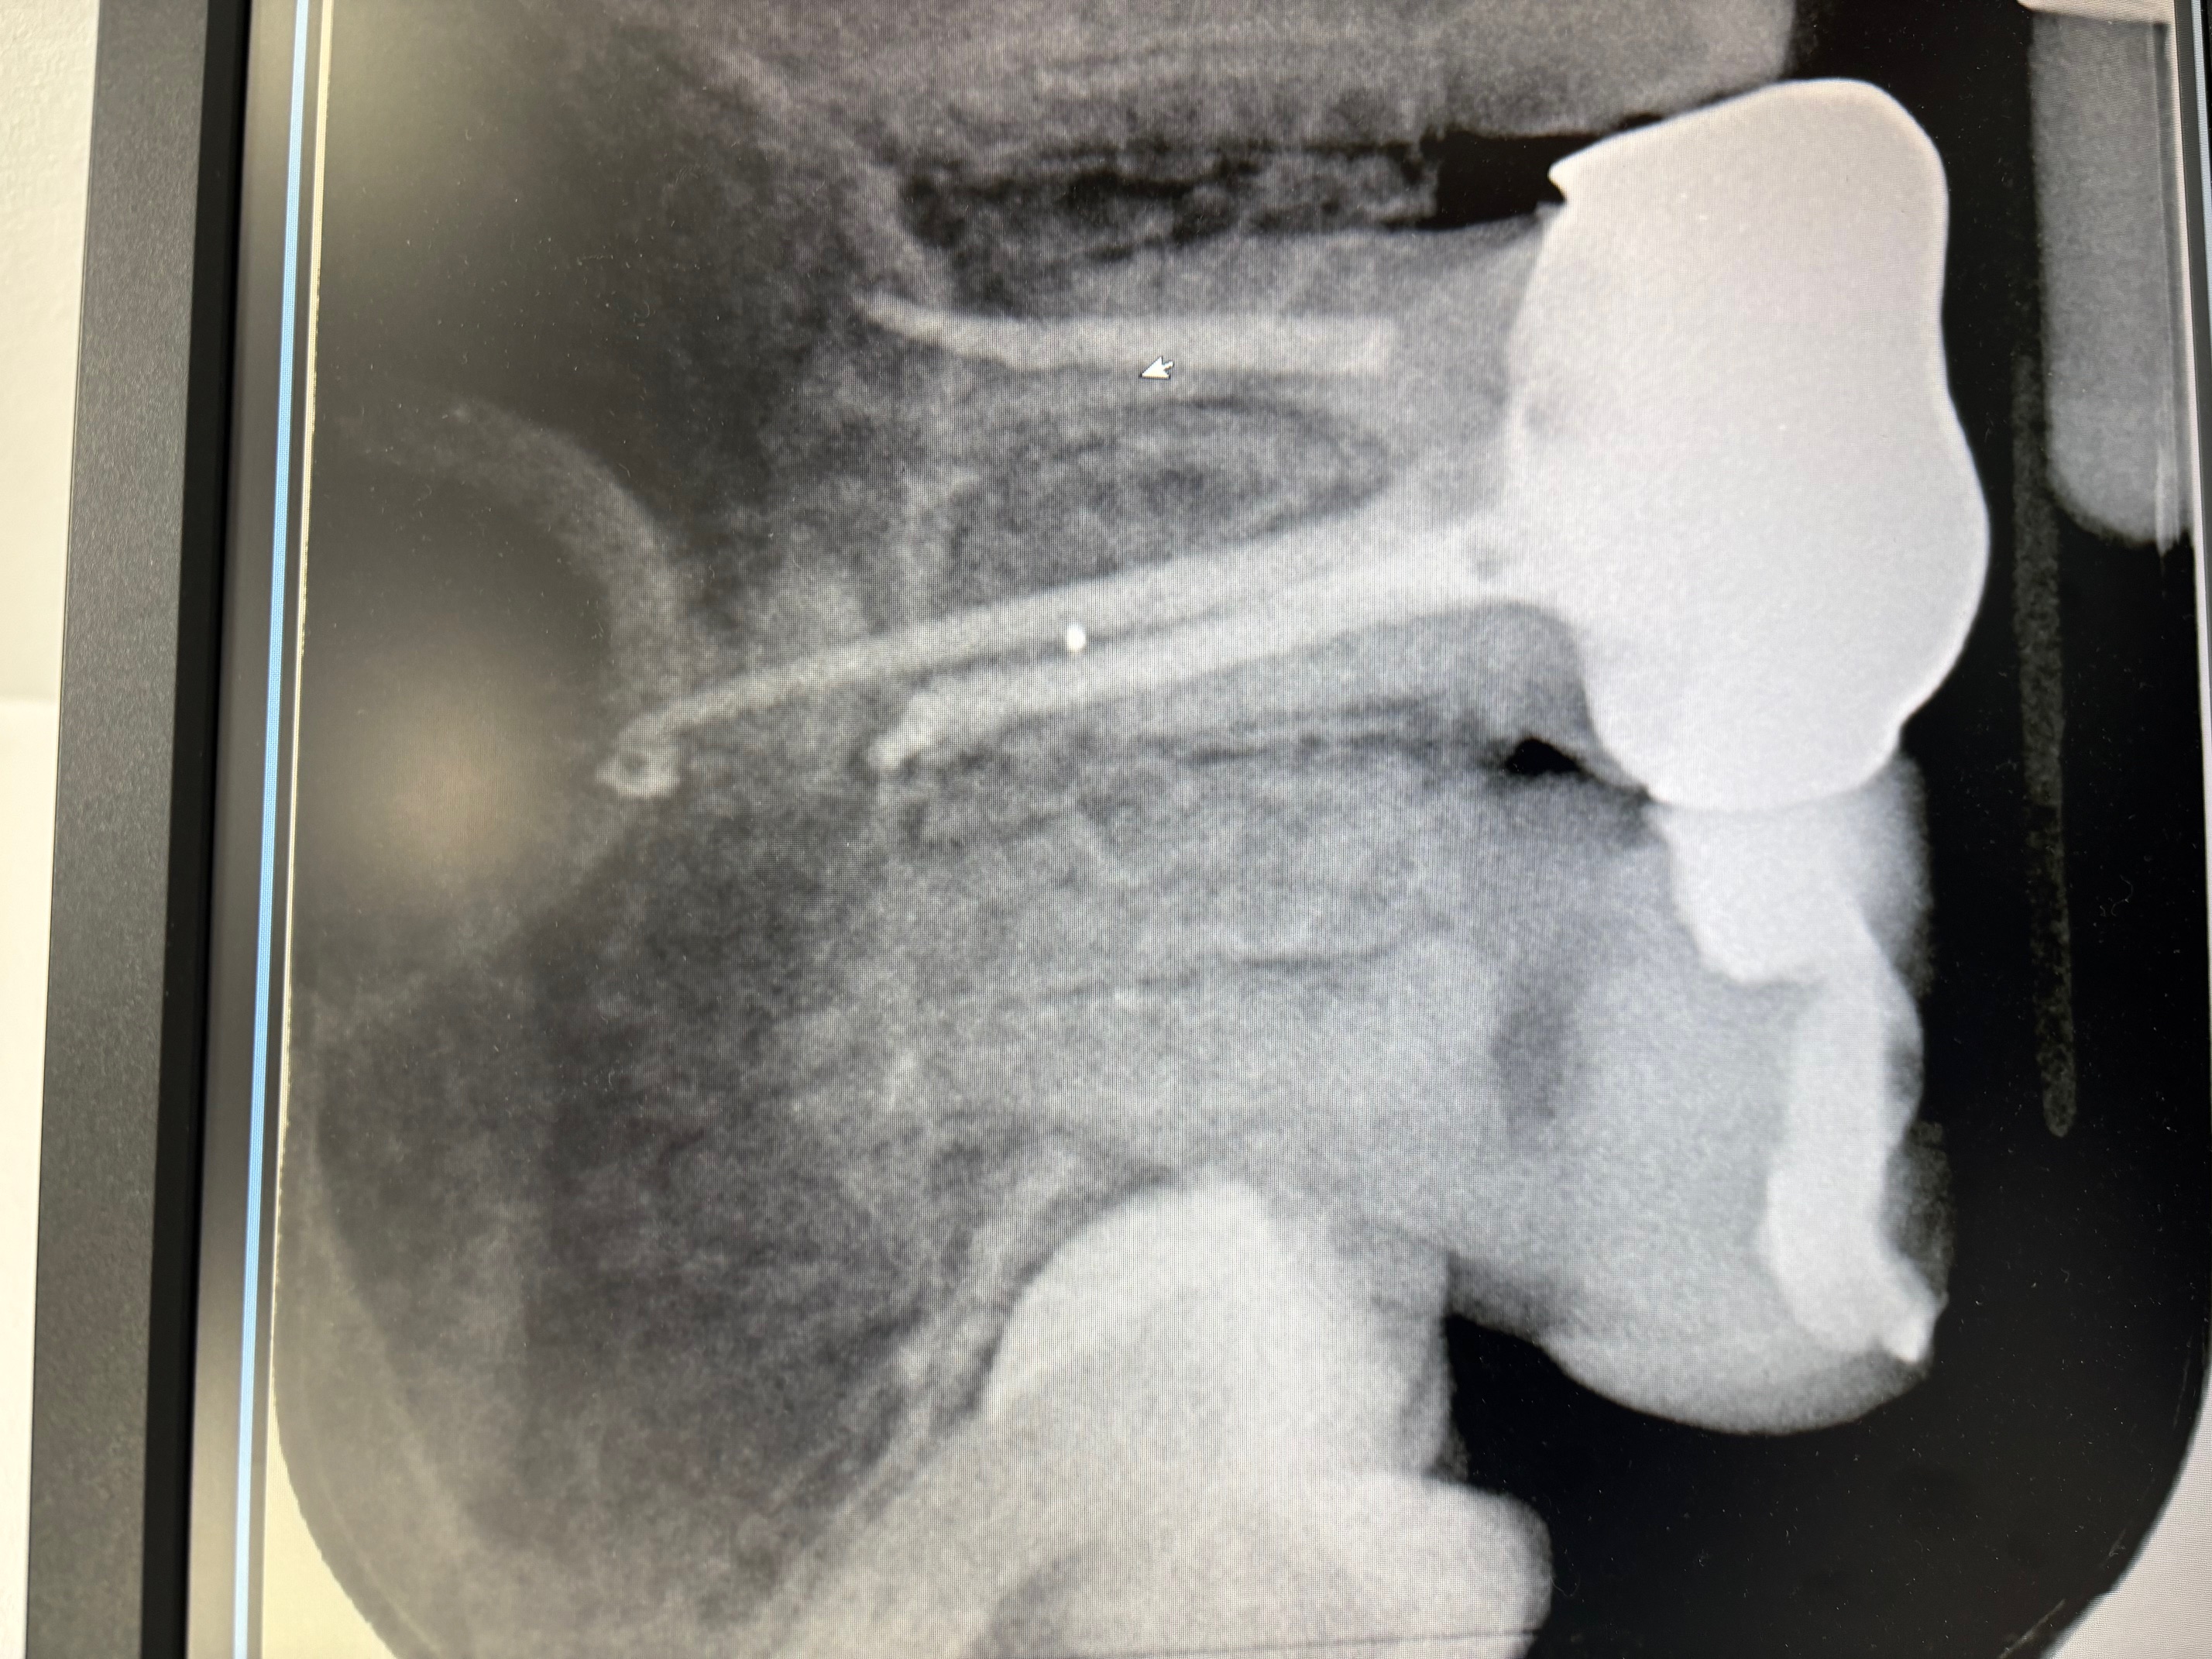

レントゲンに黒い影がありましたが、症状がなければ処置はしませんか?

回答数:2 -